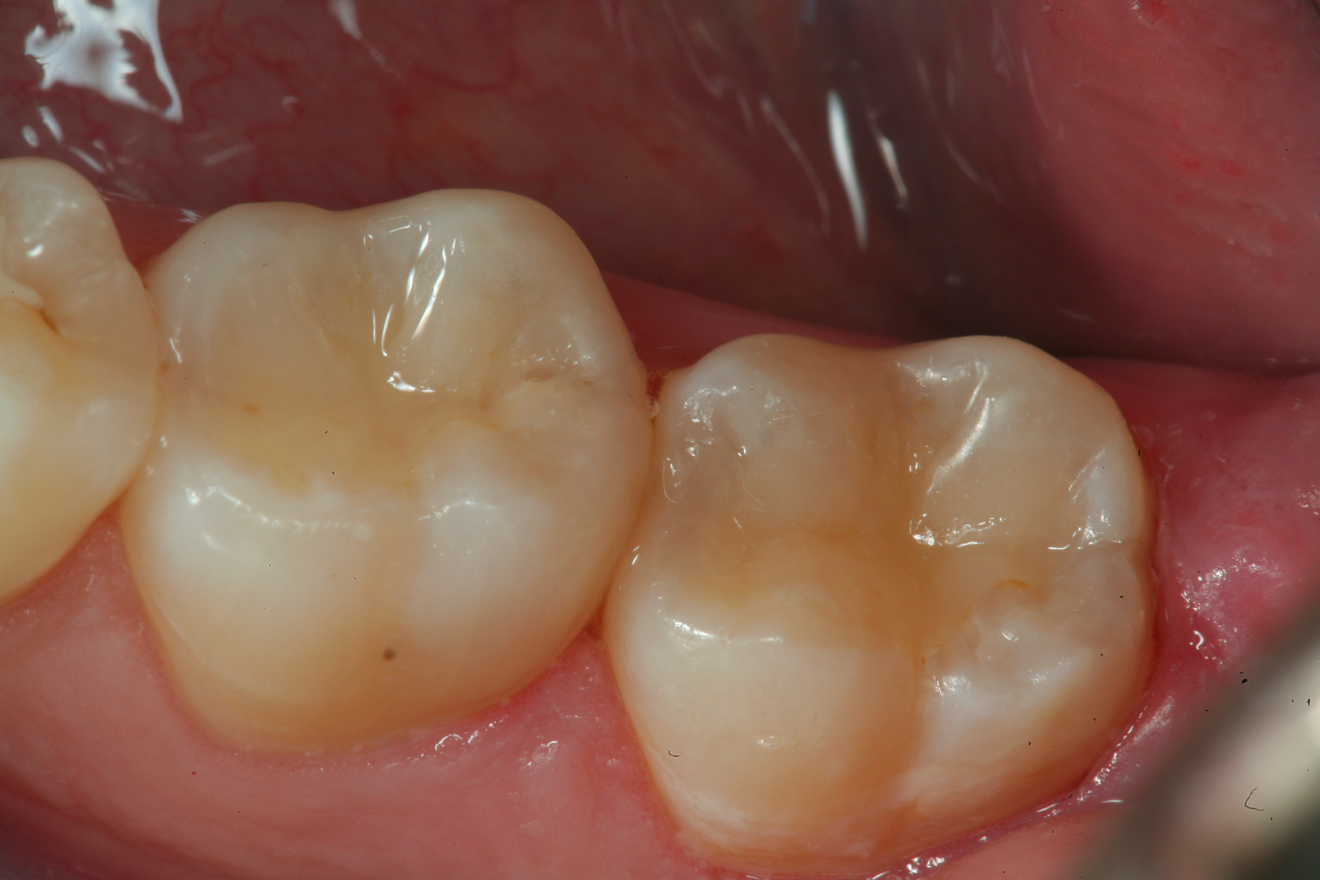

Fig 1.	A preoperative occlusal view of tooth No. 13 that has a “stain” in the occlusal groove that does not “stick” with an explorer.

Figure 1

A 66 year-old female patientpresented with a "stained" occlusal groove in tooth No. 13 that did not "stick" with an explorer tip (Figure 1).  Upon radiographic examination (Figure 2), a rather large carious lesion was discovered that encroached upon the dental pulp.  There were no other clinical or subjective signs to alert the clinician or patient to the extent of the damage that had already occurred in the tooth. Figure 3 through Figure 5 show selective caries removal using a round end plastic polymer bur (SmartBurII, SS White).  Before caries removal, isolation of the operative quadrant was achieved using Isovac (Zyris). Because of its Knoop hardness of 90, SmartBurII allows for removal of infected dentin only, while allowing affected dentin to remain for potential remineralization with a bioactive liner or base material.